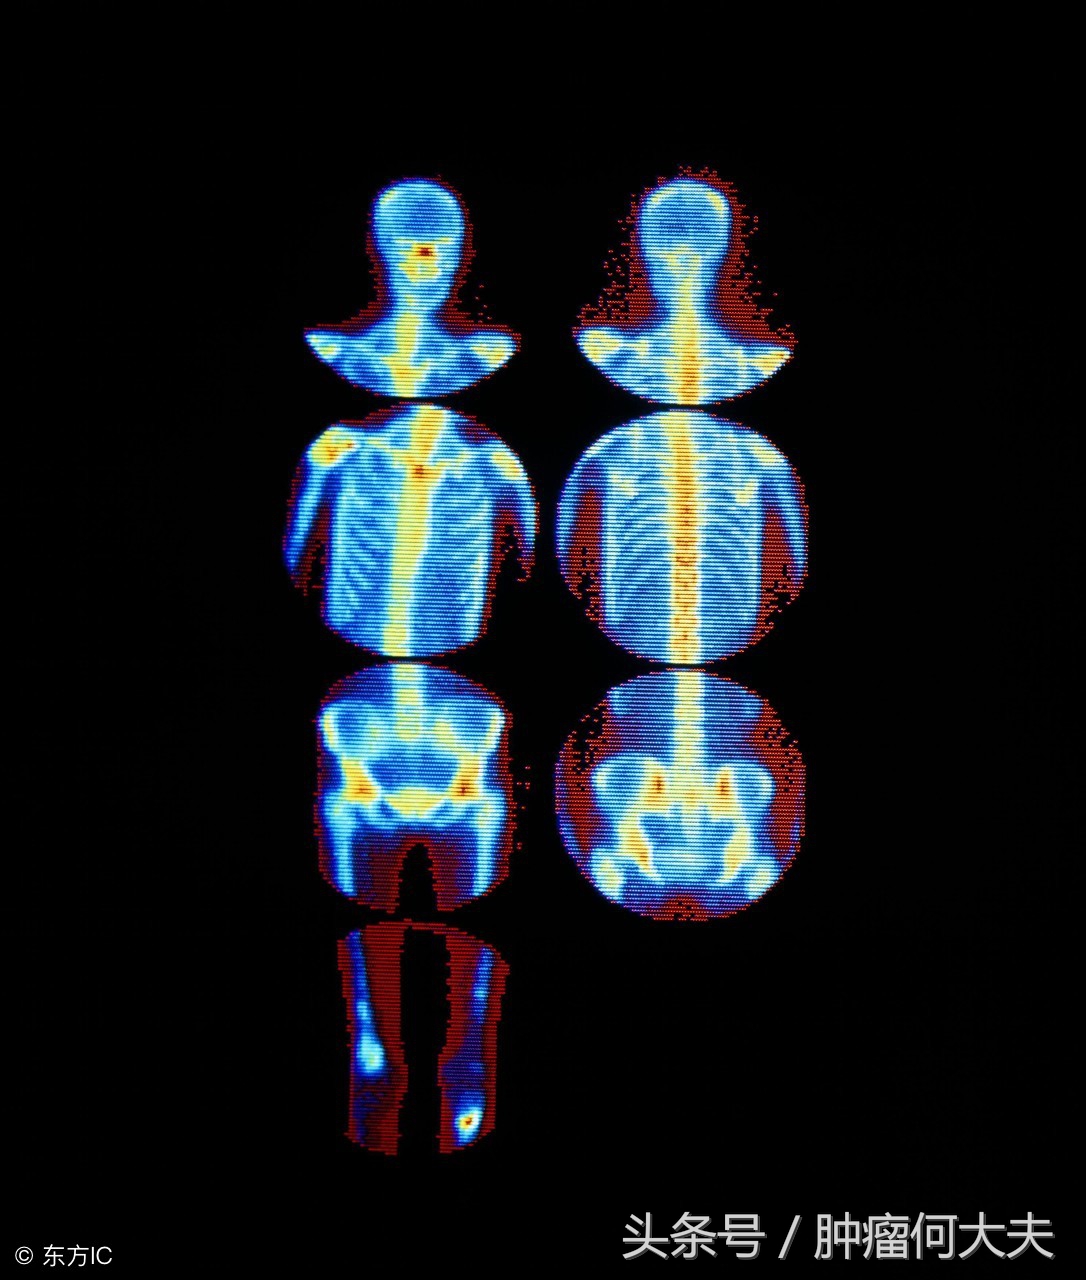

其次,怀疑骨转移要做这些特殊检查:①X线平片检查,表现为骨破坏和骨质修复共存。乳腺癌、肺癌、甲状腺癌和黑色素瘤主要表现为骨破坏、塌陷、骨折。前列腺癌表现为骨增生,成为成骨性改变。②放射性核素骨扫描,骨扫描是最常用和最敏感的方法。可比X线早发现骨转移3~6个月。③CT和MRI,可显示骨破坏和软组织肿块病灶。MRI是肿瘤脊髓压迫症的首选检查方法。